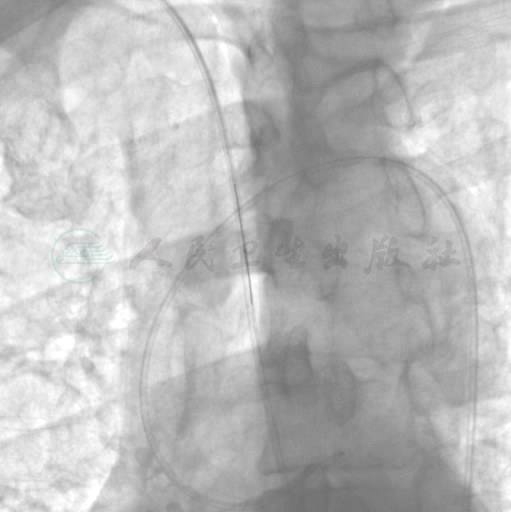

选用右侧桡动脉径路,6F血管鞘。造影发现:左主干、回旋支正常,前降支近端99%狭窄,右冠近端开口处完全闭塞,有“海蛇头”滋养血管,远端血管隐约可见(图1、图2)。

图1 右冠造影

图2 左冠造影